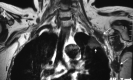

Fig 11.

A, An elongated C7 transverse process on the right (small arrow) and a cervical rib (long arrow) articulating with first thoracic rib on the left on a maximal-intensity-projection view of a neck CT of a patient presenting with cervical pain and bluish discoloration of both hands, more so on the left. MRA and MRV of the neck vessels (not shown) in abduction did not show any stenosis excluding vascular (arterial or venous) TOS. B–D, Sagittal CT (B) and sagittal MR imaging (C and D from lateral to medial) views in a neutral position on the left side demonstrate cervical rib−first rib articulation (star) and the cervical rib contacting the BPL fibers in the costoclavicular space, responsible for neurogenic TOS. The patient's symptoms on the right are due to the elongated C7 transverse process impinging the BPL within the interscalene triangle (not shown).